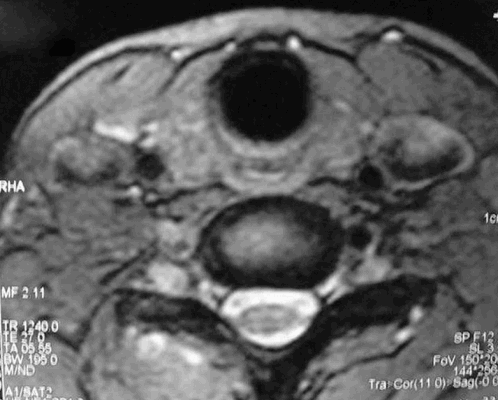

Рисунок 1,2. МРТ мягких тканей шеи (Т2-ВИ и Т1-fs-ВИ контрастное усиление). Патологических образований в структуры щитовидной железы не выявлено.